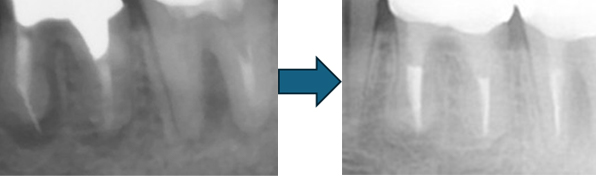

こちらのレントゲン写真を見てください。どちらかの歯医者さんで神経を取っています。根管に入れる薬は白く映ります。赤矢印部分です。一番右側が模式図ですが、青い部分が薬、根っこの先の赤点が化膿している部分です。

薬がほとんど入っていないのがわかります。黄矢印部分です。青矢印まで薬が入らないといけないのですが、全く入っていません。その結果、根っこの先が黒くなっています。膿が貯まって化膿すると黒く写ってくるのです。

別な歯科医院で治してもらいました。薬が根の先まで入っているのがわかります(黄矢印)。 根尖の黒い影が消失しています(赤矢印)。骨が再生すると白く写るようになります。

①の写真はどちらかの歯医者さんで神経を取ってもらったレントゲン写真です。根っこの中に薬が全く入っていません。

②の模式図で青く描かれている部分が薬です。

根の先を見ると小豆ぐらいの大きさの黒い影が見えます。根の中でばい菌が繫殖し感染を起こすとこのような黒い影ができます。黒い影の部分は膿(ウミ)が貯まっています。こうなると腫れて痛みが出てくるのです。

③、④の写真はそれを治した後のレントゲン写真とその模式図です。白く映っている薬が根の先まできちんと入っているのが確認できます。そして根の先にあった黒い影が消えているのが分かります。根の先の炎症が治って、骨が再生すると白く映るのです。

実はこのケース、歯医者さんの神経を取る治療でこのような根っこの病気になってしまったのです。そこでこの患者さんは神経を取った歯医者さんではなく、別の歯医者さんに受診して、根っこの治療をして治したのです。